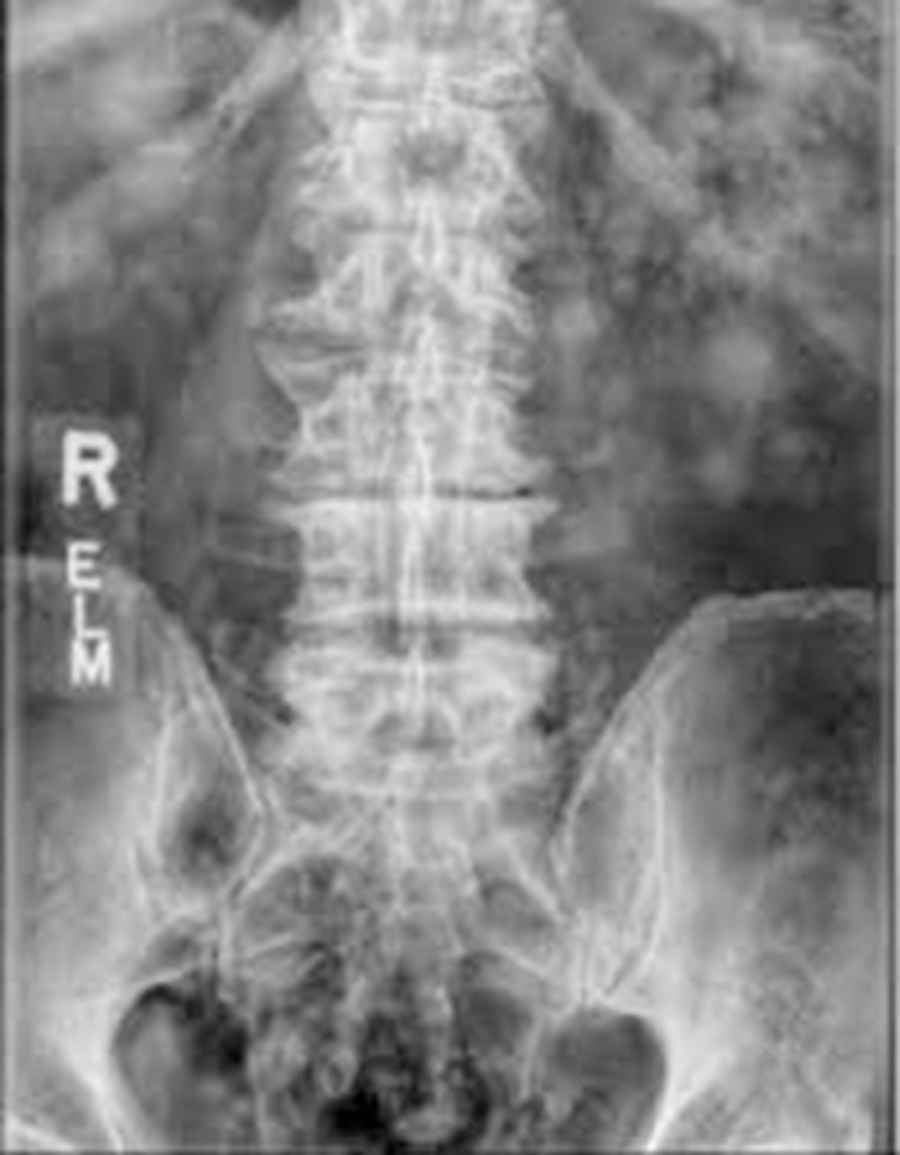

Patient medical history

A 72-year-old man with a 20-year history of chronic low back pain and radiculopathy to the right leg that was worse than to the left. An electromyography revealed bilateral L4, L5, and S1 radiculopathies. Conservative treatment failed. Discography triggered concordant pain in discs L3-4, L4-5, and L5-S1. Visual analog scale (VAS) backpain score was 90; VAS right leg pain score, 75; VAS left leg pain score, 65; Oswestry Disability Index, 56; and Roland-Morris Disability Questionnaire, 22.

The patient underwent L3-S1 anterior reconstruction with indirect decompression (utilizing the UNLEASH™ ATP Procedural Solution L3-5 and ALIF L5-S1) and Percutaneous Posterior Segmental Pedicle Screw Fixation (Fig 5). Systems used were the following:

- INSIGHT® Lateral Access System (L3-L5)

- CONDUIT™ Lateral Interbody (L3-L5)

- CONDUIT™ ALIF Interbody and Aegis plate (L5-S1 with SYNFRAME® Access and Retractor System)

- VIPER PRIME® Screws: Posterior Pedicle Screw Instrumentation L3-S1